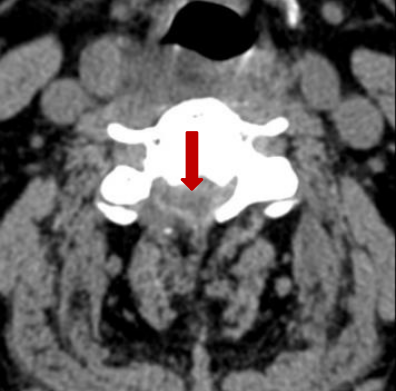

术前脊髓造影后颈椎CT。

颈椎间盘突出明显。